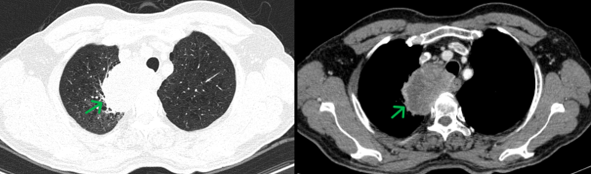

- Chụp cắt lớp vi tính lồng ngực (20/08/2024): Thùy trên phổi phải có khối đặc kích thước ~ 67x39mm, bờ không đều, ngấm thuốc sau tiêm không đồng nhất, dày tổ chức kẽ dạng lưới và kính mờ xung quanh, lân cận có nốt kính mờ đường kính ~5mm, phát triển vào trung thất, đẩy khí quản và thực quản lệch trái, có phần không rõ ranh giới với thành thực quản đoạn ngang mức. Phổi trái giãn phế nang trung tâm tiểu thùy và cạnh vách chủ yếu thùy trên. Trung thất, rốn phổi phải có vài hạch kích thước ~13x17mm, ngấm thuốc không đều sau tiêm.

Hình 1. Hình ảnh khối u thùy trên phổi phải (mũi tên xanh) kích thước 67x39mm, bờ không đều, ngấm thuốc sau tiêm không đồng nhất.

Hình 2. Hình ảnh hạch rốn phổi và hạch trung thất (mũi tên đỏ) kích thước khoảng 13x17mm